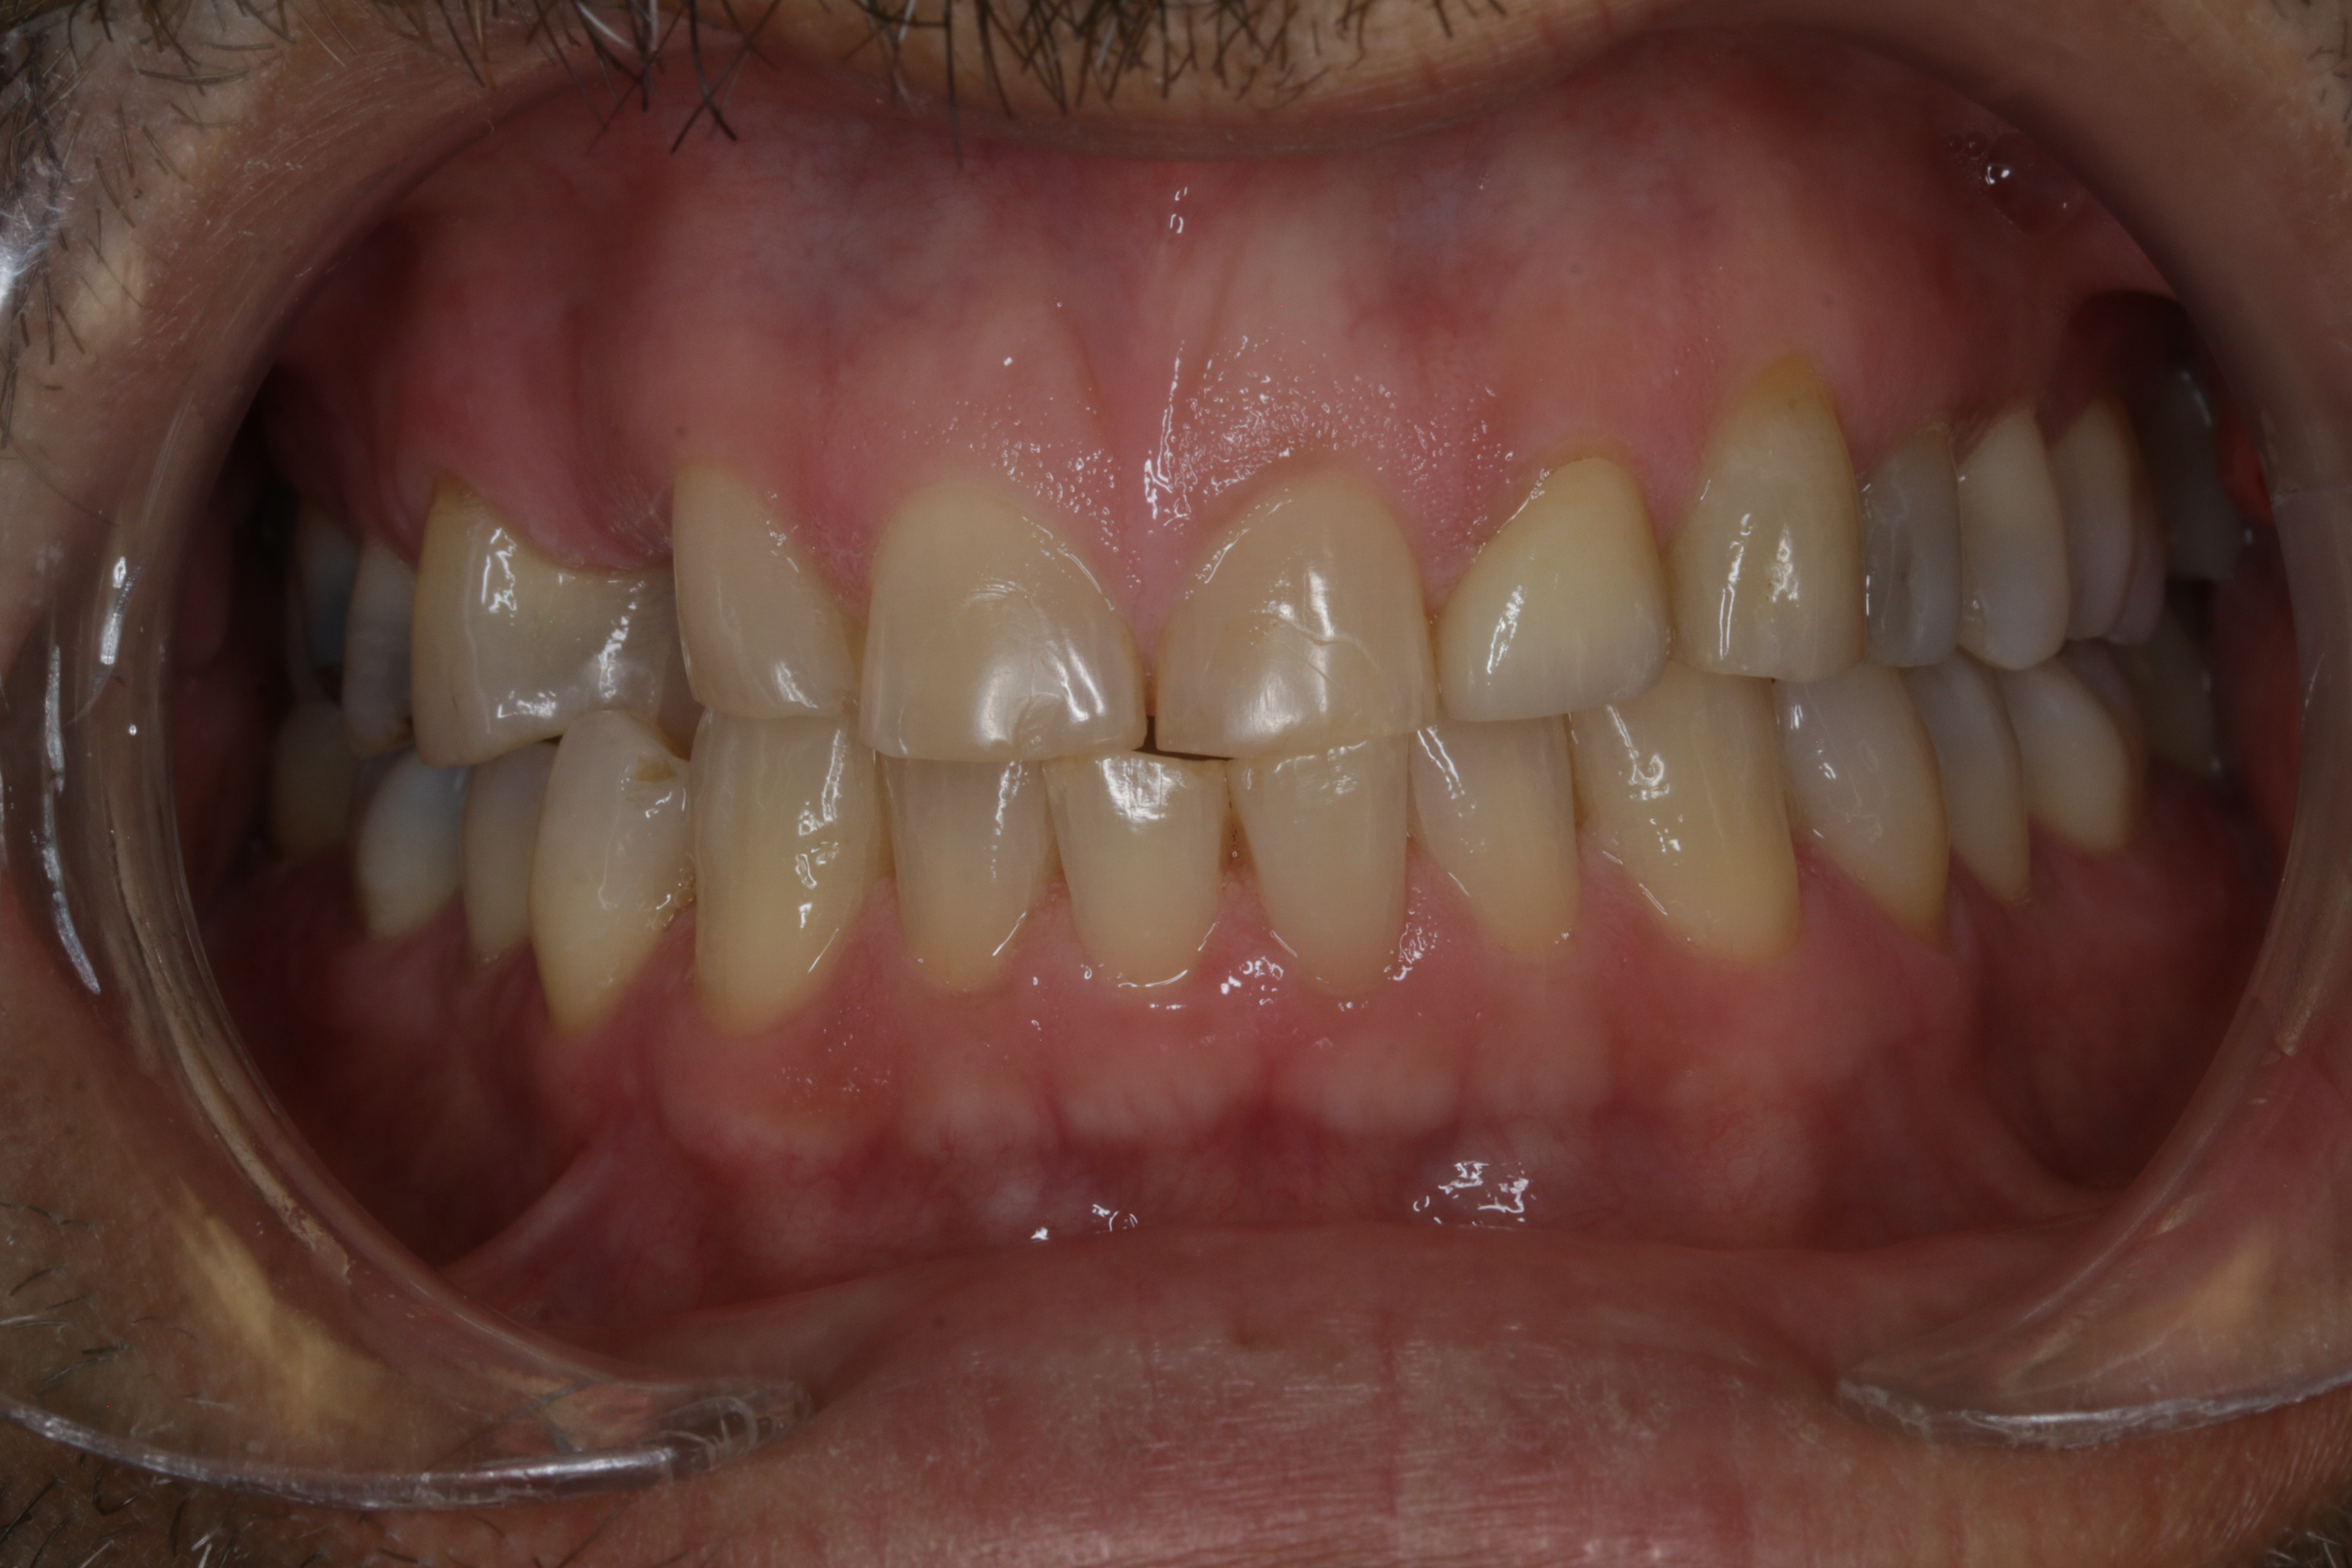

INITIAL RECORDS

BEFORE

BEFORE LEFT SIDE

BEFORE RIGHT SIDE